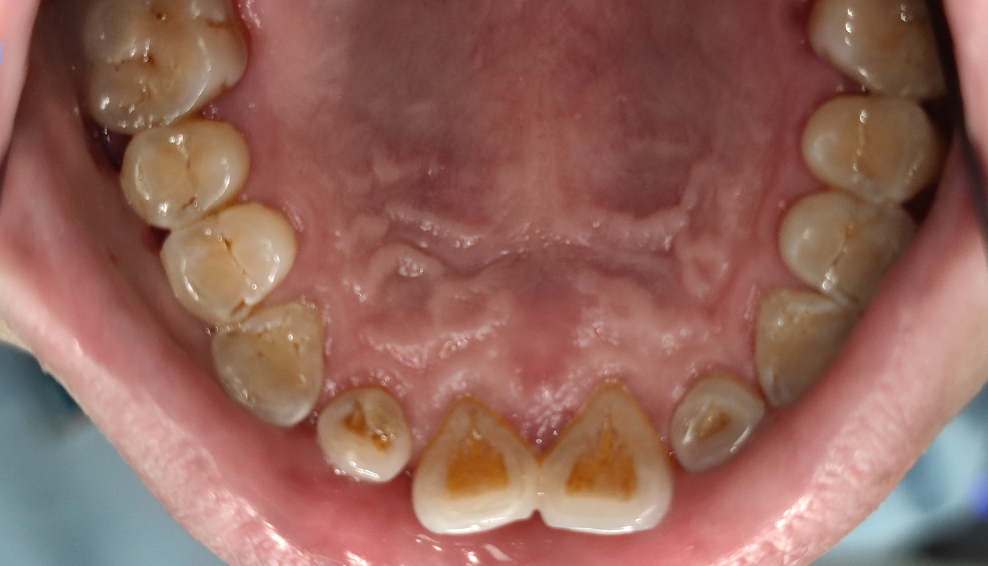

廊坊济民口腔医院科普-牙结石是如何形成的?

牙结石形成的原因来自很多方面,主要有以下几点推论:

唾液中的二氧化碳浓度降低,促使无机盐沉淀于牙齿表面上。

退化细胞的磷酸盐酵素使有机磷水解产生磷沉淀于牙齿表面而形成。

由于细菌使唾液的酸碱值升高而呈碱性,造成唾液中的蛋白质分解,放出钙盐,沉淀于牙齿表面上而成。

与口水浓度有关,浓度愈大,愈易沉淀。

另外,牙结石形成的速度、形态和硬度因人而异,一般来说新生牙结石只需12-15小时。快速形成的牙结石要比慢慢形成的牙结石要软且碎。